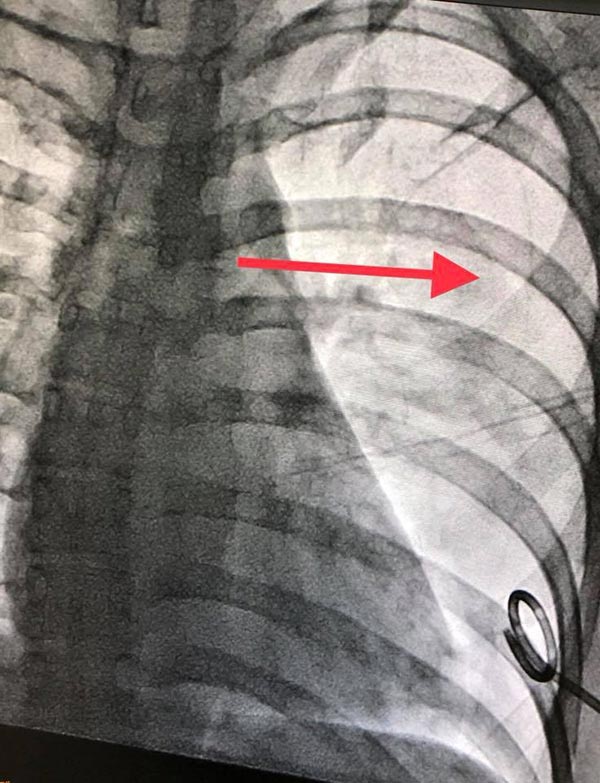

โดยผลตรวจร่างกายด้วยการเอกซเรย์ พบว่า ปอดข้างซ้ายมีอาการแฟบมากถึง 50% เนื่องจากมีลมที่คาดว่ารั่วจากปอด กดทับปอดเอาไว้ ทำให้พองตัวไม่เต็มที่เมื่อหายใจ

ทั้งนี้ นพ.มนูญ ได้นำภาพเอกซเรย์แสดงการรักษาของคนไข้ ซึ่งใช้วิธีต่อท่อระบายอากาศ ให้ลมออกจากร่างกาย คาดว่ามีลมนอกปอดมากกว่า 300 ซี.ซี. ก่อนให้คนไข้กลับบ้าน จากนั้นประมาณ 1 สัปดาห์ ปอดก็กลับมาใช้งานได้ตามปกติ